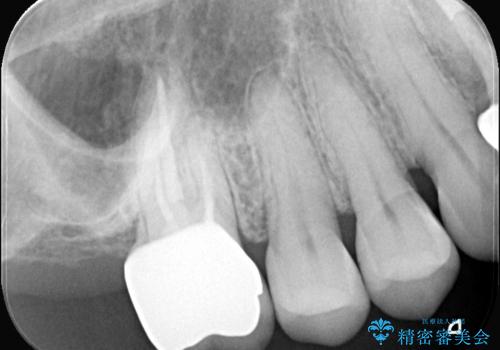

詰め物が外れた奥歯。MB2の発見

- 「奥歯の詰め物が取れた」という主訴でご来院されました。レントゲンおよび視診の結果、詰め物が外れた内部で虫歯が再発しており、根の先にも炎症が見られたため、再根管治療(根の再治療)が必要と診断しました。 特に上顎の大きな奥歯(第一大臼歯)は、通常の根管以外に「MB2」と呼ばれる隠れた根管が存在することが多く、これが未処置のままだと再発の原因となります。そこで、歯科用顕微鏡(マイクロスコープ)を用いて徹底的に内部を清掃し、その後、強度と審美性に優れたオールセラミッククラウンで修復する計画を立案しました。

顕微鏡によるMB2の発見: 歯科用顕微鏡(マイクロスコープ)を使用し、根管内を強拡大して観察したところ、事前の予想通り、従来の治療では見逃されていた**第4の根管「MB2」**を発見しました。この未処置だった根管内の汚れを徹底的に除去・消毒することで、痛みの再発リスクを根本から取り除きました。